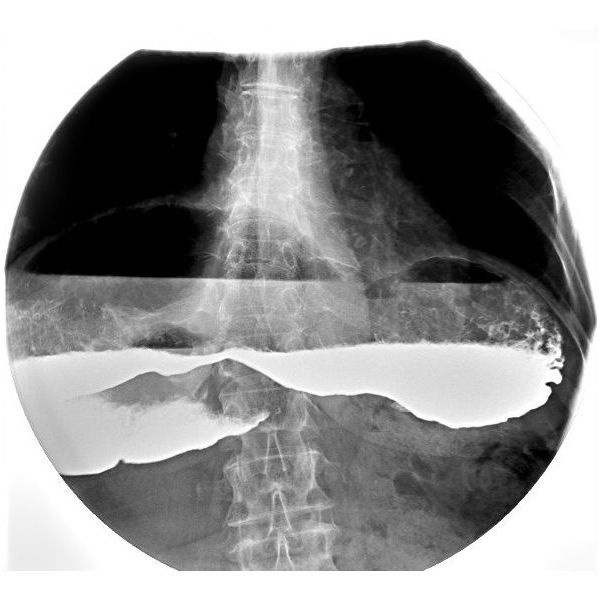

Рентгеноскопия пищевода и желудка с контрастированием выявила:

- сильное увеличение и растяжение желудка (внутри определялось большое количество остаточного содержимого);

- замедленное передвижение контрастного вещества из желудка в 12-перстную кишку (снимок, сделанный через 2 часа, показал, что часть контрастного вещества всё ещё оставалась в желудке);

- обратный заброс желудочного содержимого в пищевод.